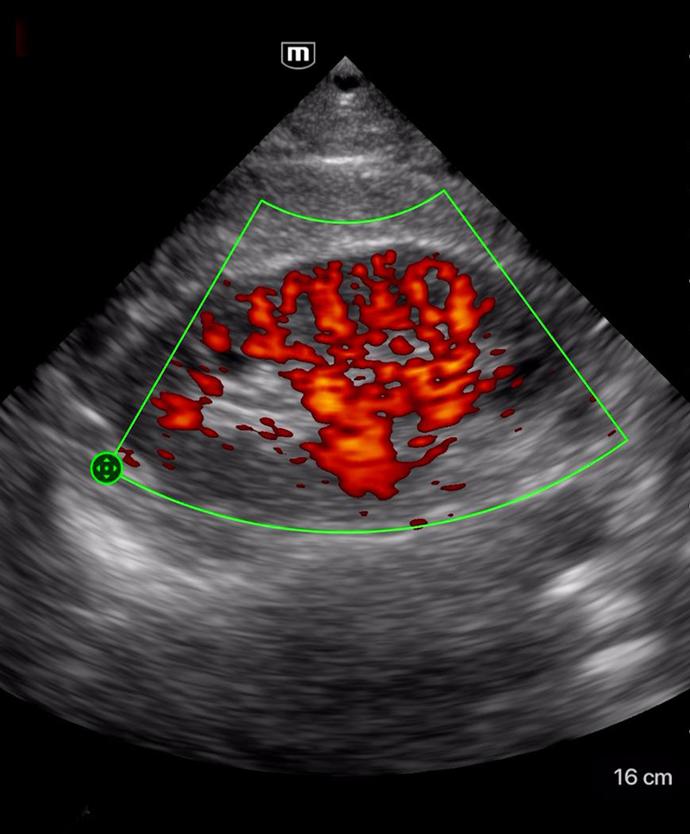

Множество режими за сканиране

Color mode

Клинични снимки